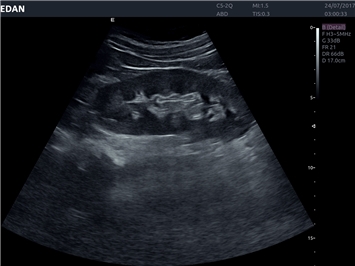

• Общей визуализации

• Акушерства и гинекологии

B-режим, Двухмерное сканирование:

Да